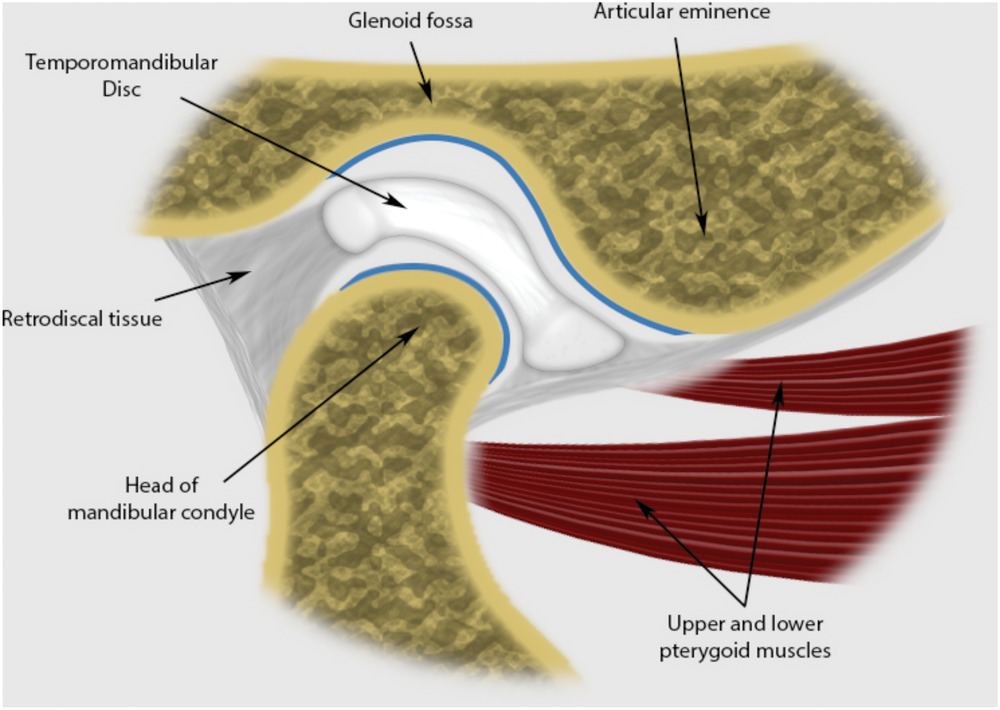

TMJ

Join capsule

Articular eminence 到 articular fossa

Joint disk

-

分成 Ant. band(2mm), Central intermediate zone(1mm),

Post. band(3mm) -

Dense fiber CT,無神經血管

-

Lower division 連到 condylar neck 的 lat.,med. poles

-

Upper division 連到 Temporal bone 的 postglenoid process

collateral ligament

retrodiskal tissues

有神經血管,分秘 Synovial fluid 到 Synovial cavity

- Superior retrodiskal lamina:elastic fibers,接到 tympanic plate,限制平行移動

- Inferior retrodiskal lamina:Collagen fibers,將 disc 接到 condyle,限制旋轉移動